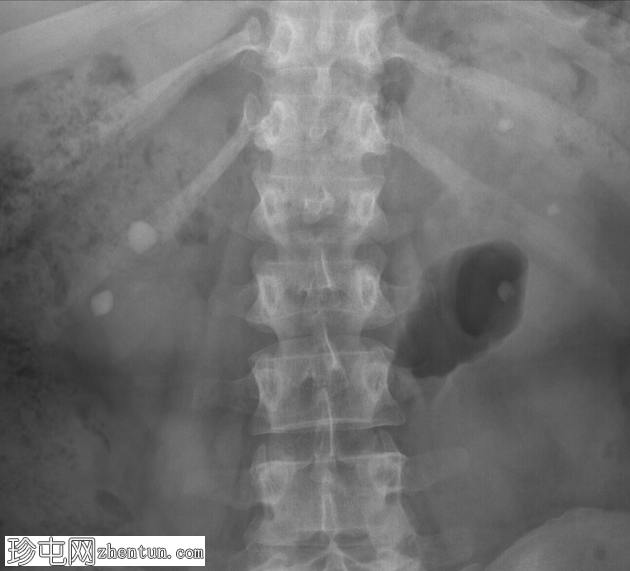

正位片

右肾下盏和中盏可见边界清晰的圆形不透光影,直径分别为10毫米和12毫米。注意左侧上盏、中盏和下盏内各有三个较小的不透光影。

双侧肾结石病例。